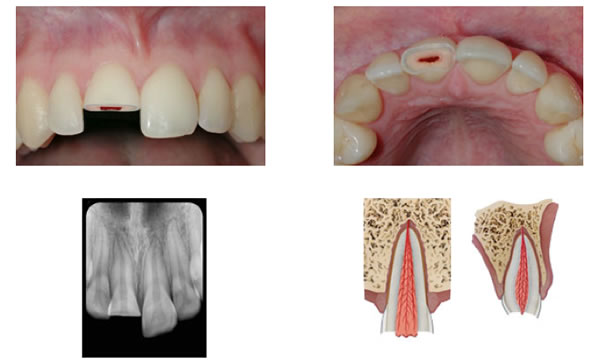

Figure 5. Vital pulp therapy of a complex crown fracture (A) can be achieved via pulp capping (B) or partial pulpotomy (C). The white material pictured directly capping the pulp can be calcium hydroxide, glass ionomer, or MTA.

Pulp capping(Figure 5) is performed by rinsing the exposed pulp tissue with sterile saline and/or chlorhexidine. Sodium hypochlorite, the workhorse of endodontic irrigants, is contraindicated in this circumstance as it will further dissolve the vital tissue that your are trying to save! After proper hemostasis is achieved, the pulp is covered with a small amount of calcium hydroxide, GI cement, or MTA (mineral trioxide aggregate) and then covered with a composite restoration. Ideally the pulp will remain vital and then form a layer of protective tertiary dentin (more specifically reparative dentin) directly beneath the capping material. On a side note…tertiary dentin is simply new dentin that is deposited in response to a caustic stimulus (carious lesion, cavity preparation). This calcified material can be formed by existing odontoblasts (reactionary) or by newly differentiated odontoblast-like cells following the destruction of the original layer of odontoblasts (reparative).

Back to VPT…A partial pulpotomy(Figure 5), sometimes referred to as a Cvek pulptomy, is a very similar to pulp capping but involves the removal of inflamed pulp tissue to at least 2mm beneath the exposure site in an attempt to reach clinically healthy pulp. This is achieved by using a high speed diamond bur with copious irrigation. Again the pulpal tissue is rinsed with sterile water and/or chlorhexidine until the bleeding has stopped and then covered with one of the three capping agents as previously mentioned. The tooth is then restored with composite. One of the benefits to performing a pulp cap or a partial pulpotomy is that there is typically enough coronal pulp tissue remaining in the pulp chamber to allow for accurate vitality testing during follow-up visits.